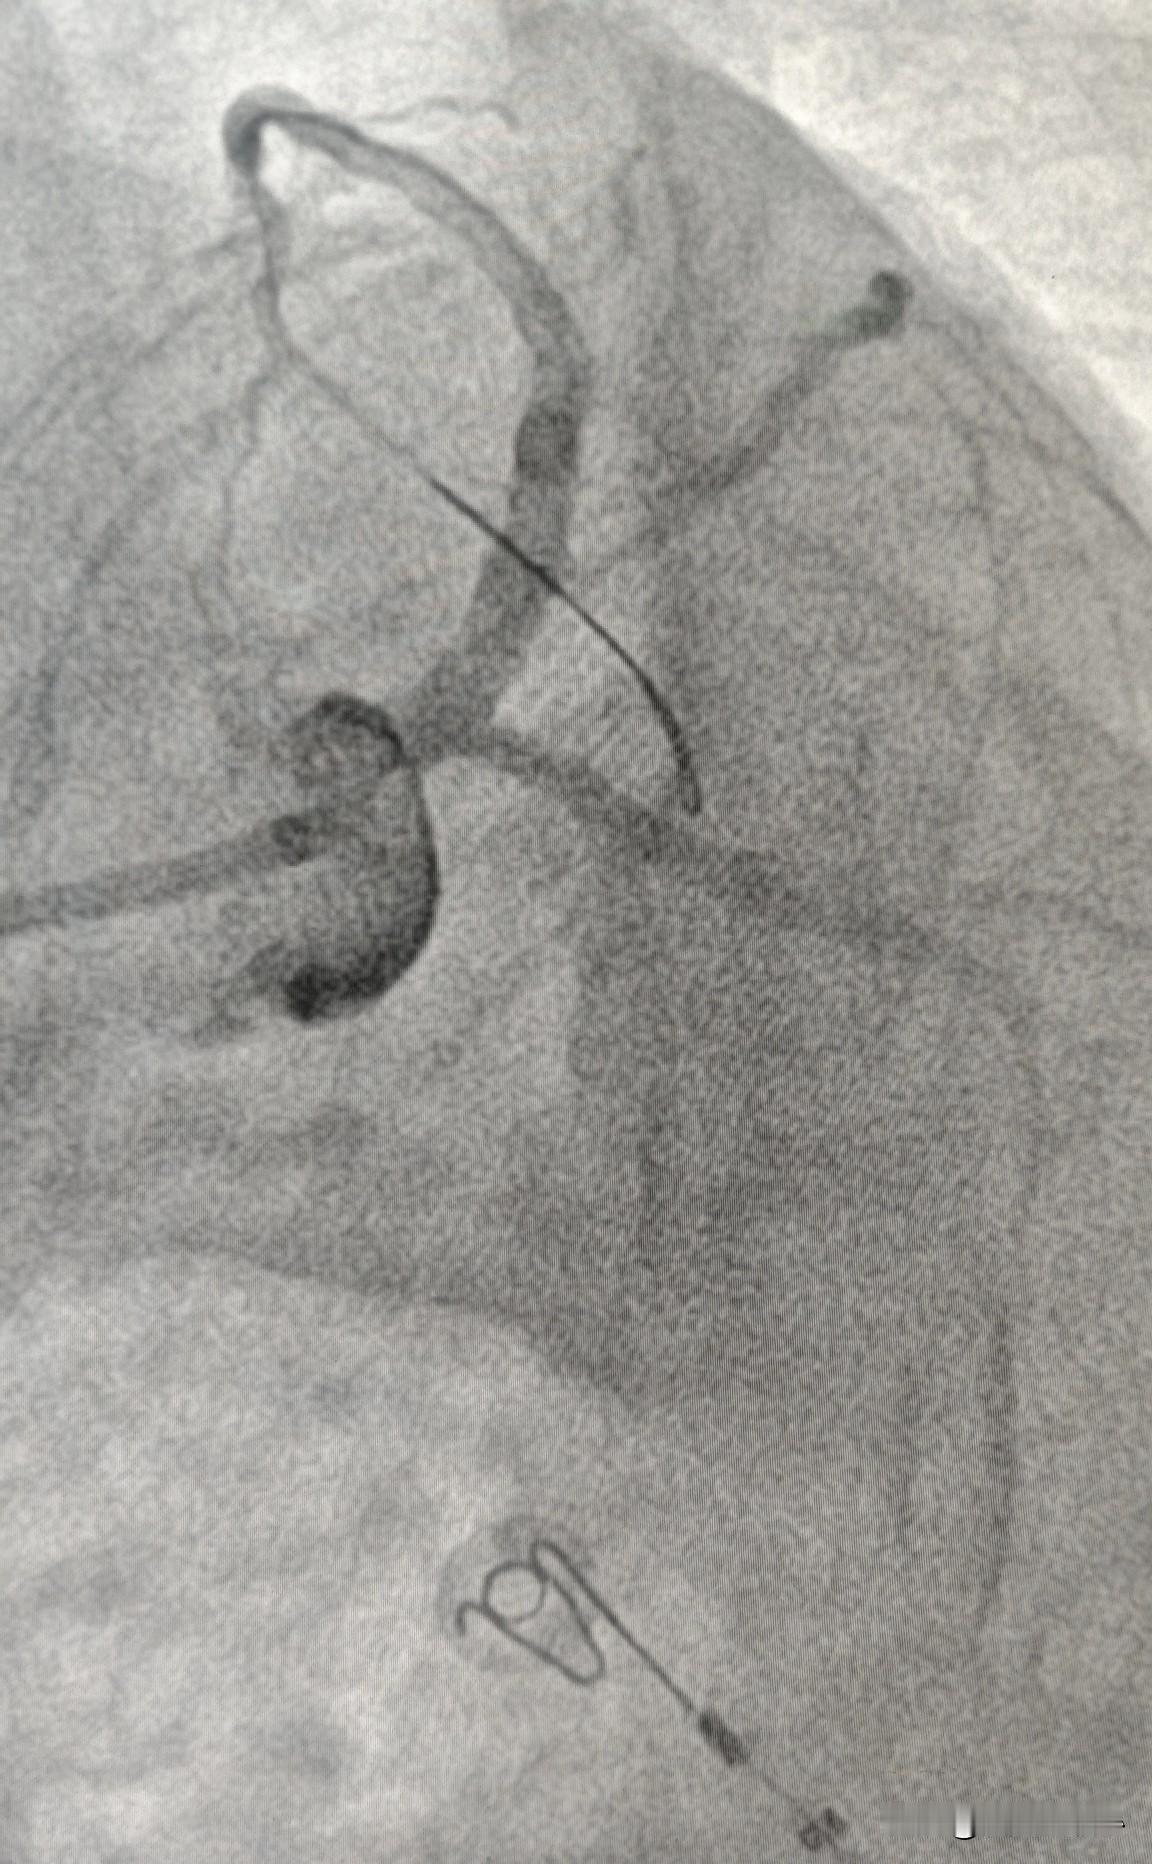

82 岁老人做冠脉支架,风险还是高一些。82 岁男性,频繁发作胸痛,做了冠状动脉造影检查发现左主干和前降支近段狭窄严重,按道理讲应该做冠脉支架治疗。但考虑到年龄大,风险高,经常看科普的朋友应该都知道,主干病变非同小可,操作过程稍有不慎,会直接休克、心脏骤停。患者也是犹豫不决,药物治疗了几个月,还是稍有活动就发作胸痛,完全没有生活质量。最后决定搏一把。 图一显示左主干和前降支近段狭窄严重。操作过程中,果然导丝在通过这段血管时,血压和心率就明显下降,出现了血流动力学不稳定的状态。一边紧急静脉推注升压药物,一边快速扩张血管,改善供血。快速把支架从前降支做到左主干后,症状终于缓解,血压也恢复到正常了,安全回到病房。 年龄大了,身体机能差一些,身体的耐受性也差一些。要是这个患者只有 60 多岁,就不会出现血压和心率骤降的情况。